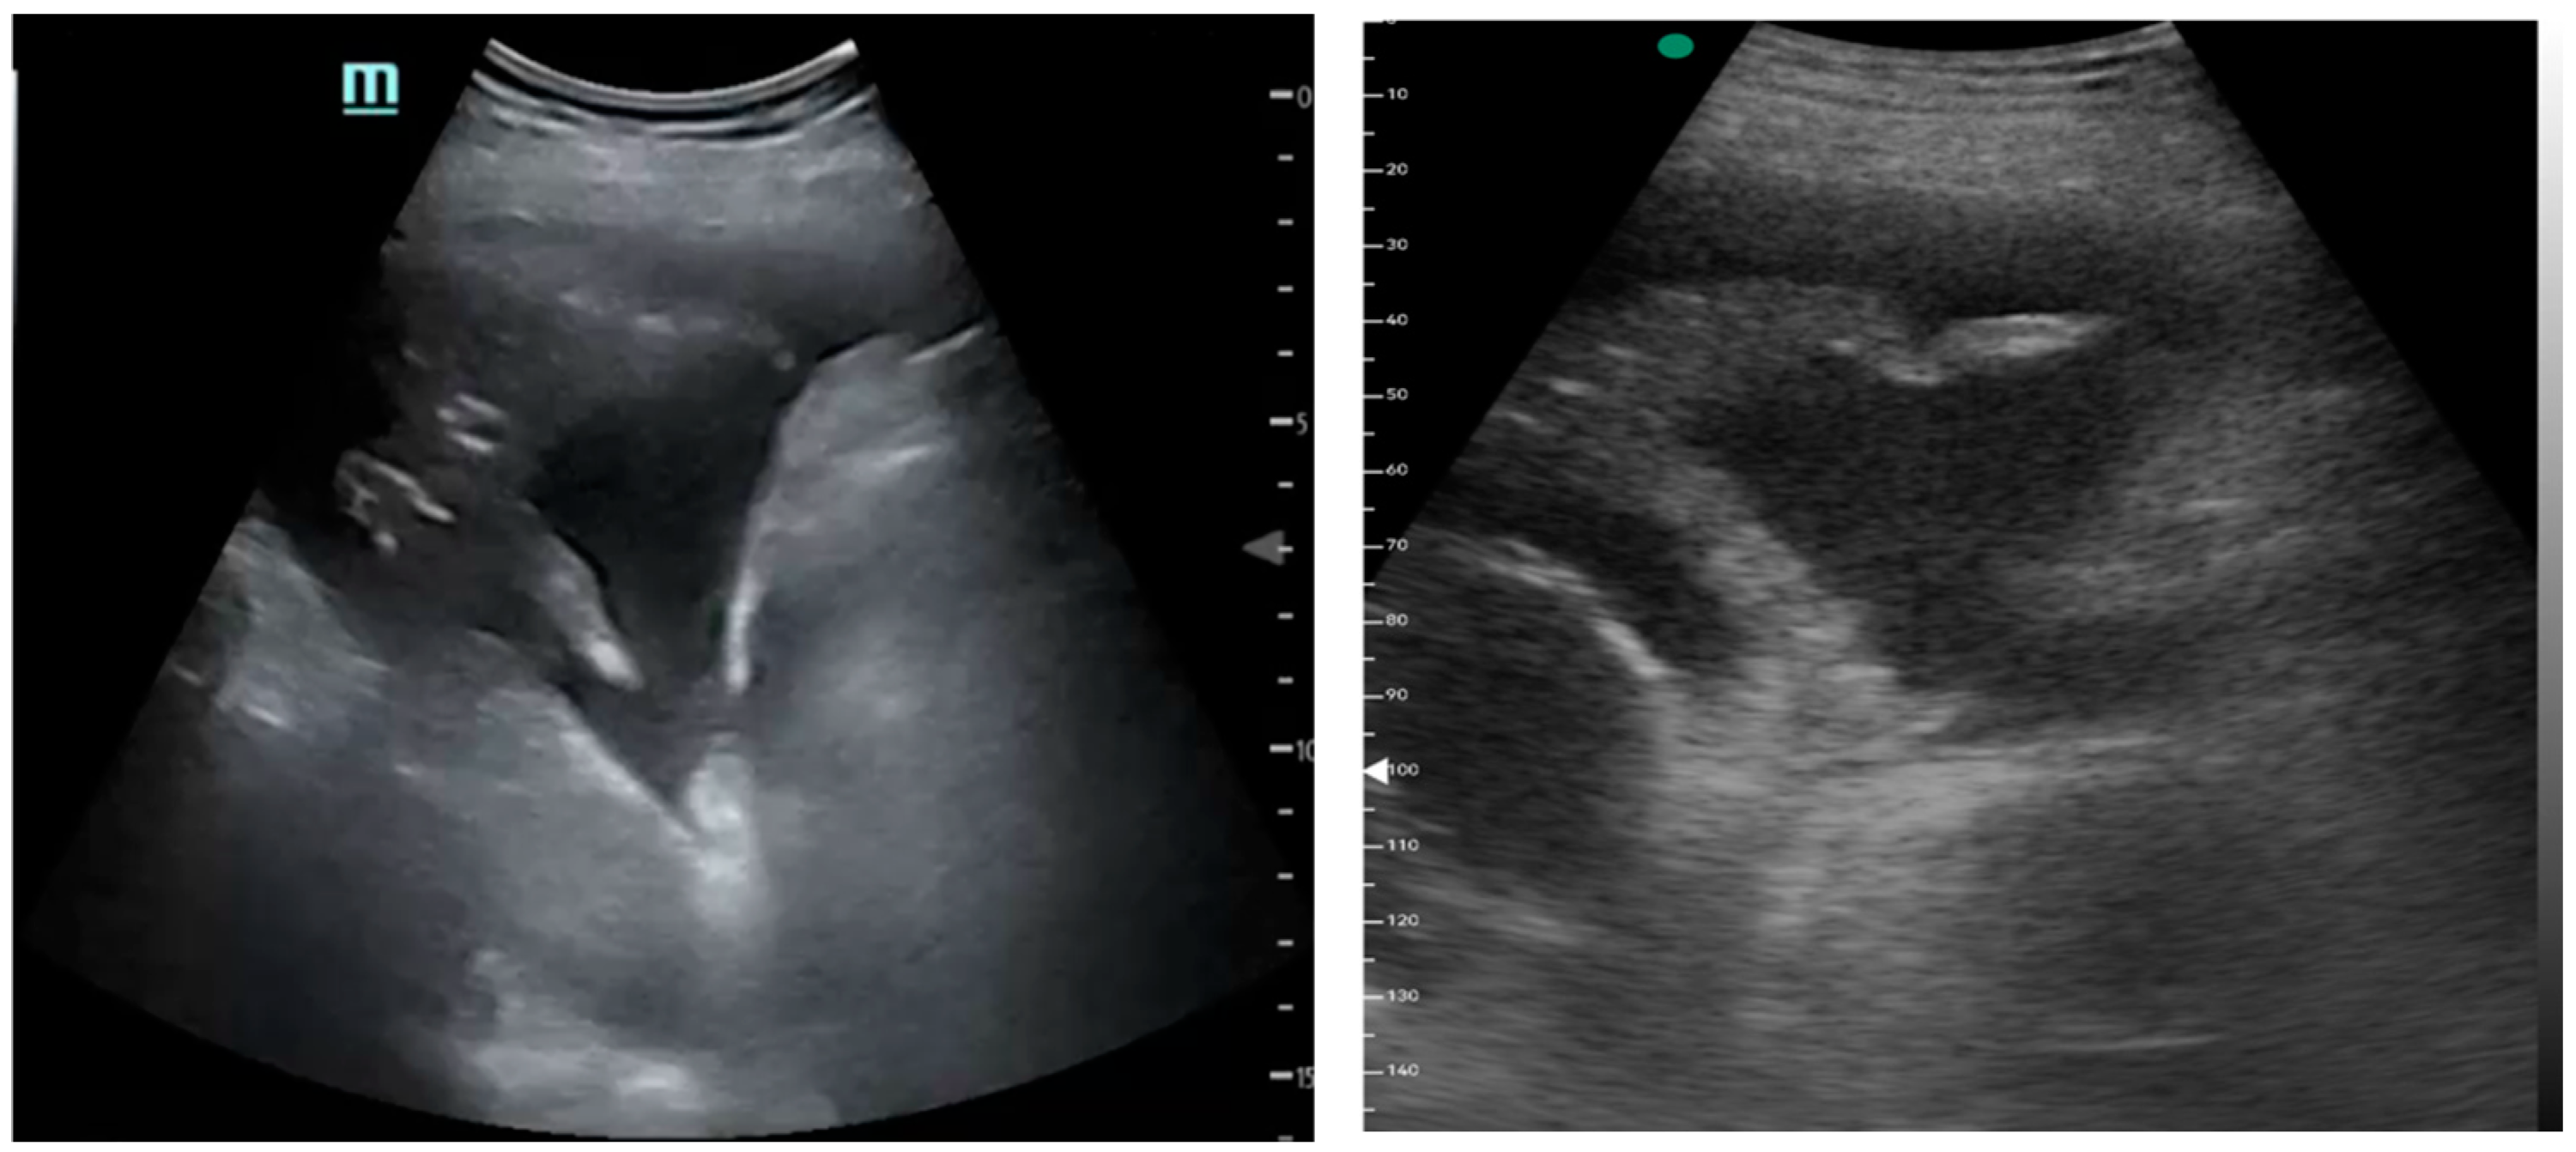

Figure 1, Figure 2 and Figure 3 exhibit characteristic examples of ultrasound still images from the videos captured via a standard ultrasound (left side) and portable handheld device (right side). Quality may slightly differ from that of the videos as these are still images.

Figure 3.

Simple pleural effusion with atelectasis.